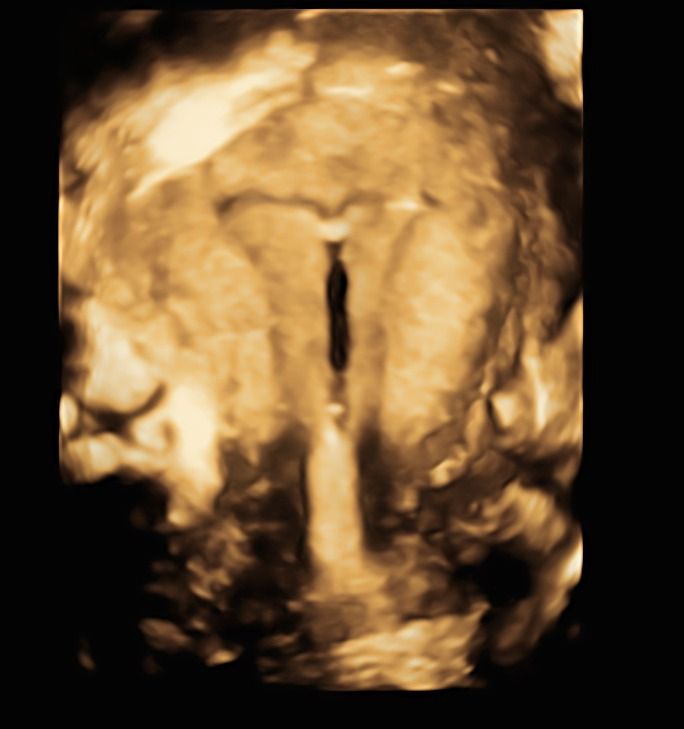

Nel corso della mia lunga esperienza lavorativa in ospedale,  ho maturato una particolare competenza nella gestione delle gravidanze a rischio sia per problematiche materne che fetali, nella diagnostica prenatale sia invasiva ( amniocentesi, villocentesi) con all'attivo migliaia di procedure effettuate, che nella diagnostica strumentale ecografica ( ecografie ostetriche di I e II livello, test combinato, studio della Translucenza nucale, DNA fetale, studio doppler flussimetrico dei distretti materni e fetali ).

Foto e video